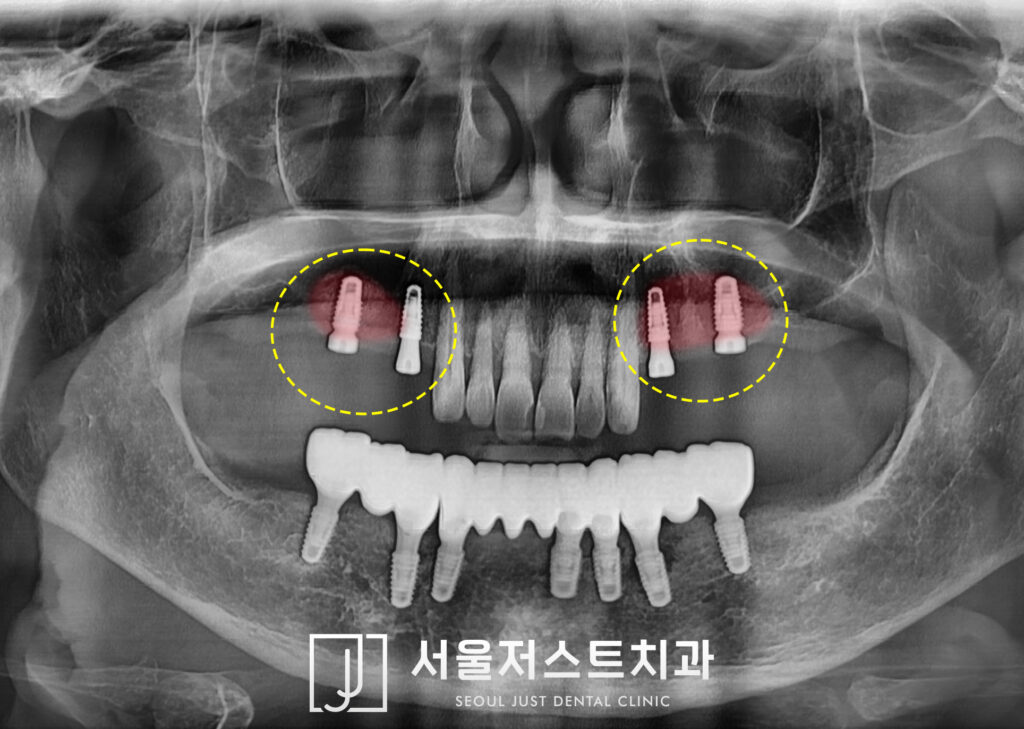

뼈가 얇았던 위쪽은 양쪽 모두

상악동 거상술 측방 접근법을 통해

많은 양의 뼈이식 후 임플란트를 식립하였는데요.

아래쪽은 빠르게 7개의 임플란트를

식립하여 2개월 후 최종 보철물을

마무리할 수 있었으며

위쪽은 잇몸 위로 뚜껑을 올려주는

2차 수술 과정을 거치도록 하였습니다.